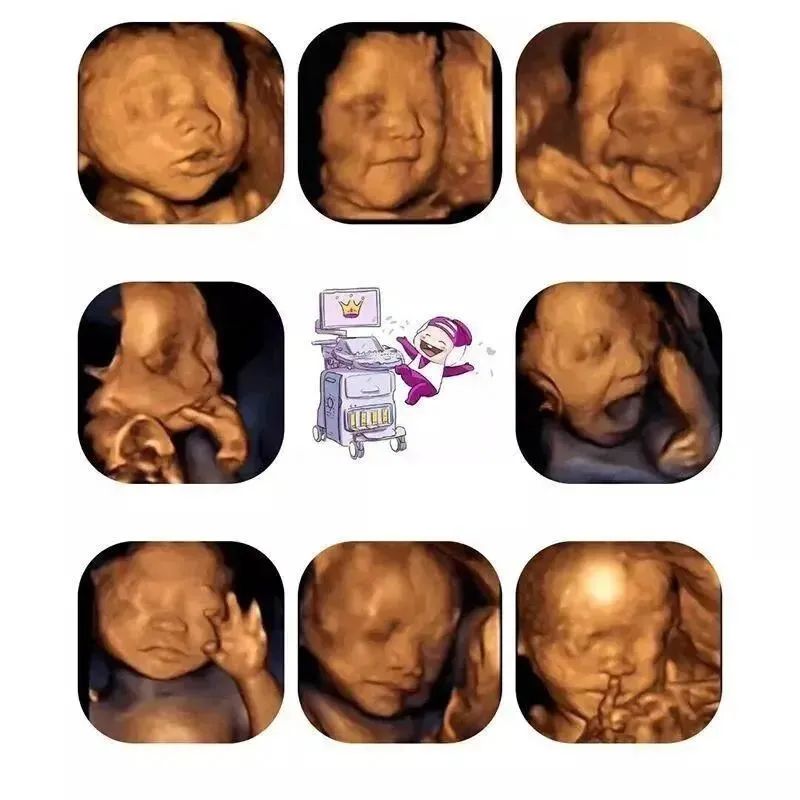

后,这张图给到大家:艾玛妇产的胎儿系统超声主要包括中枢神经系统、颜面部、心脏、胸腔、腹壁、腹腔、四肢、常规胎儿评估等方面内容。

我们会通过四维技术把胎宝宝的活动状态和长相,做成图片和视频,免费赠送送给孕妈妈们,后提醒宝妈们,做四维重要的目的还是筛查宝宝的发育状况哦,咱们不要本末倒置了。